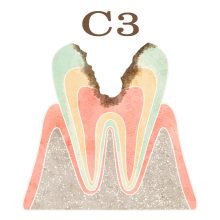

「C」とは歯科検診でよく使われる記号で、”caries”(カリエス、つまり虫歯)の頭文字を表します。「C」の後につくアルファベット(O)や数字(1,2,3,4)は、虫歯の進行具合を示します。

・C3(シースリー): 虫歯が象牙質の下にある歯髄(しずい)という歯の神経にまで進行した段階を指します。この段階では、虫歯の症状がさらに進行し、より強い痛みを伴うことがあります。C3段階の虫歯は、重度の状態であり、歯髄への感染や炎症が起こっている可能性が高いため、早急な歯科医の治療が必要です。